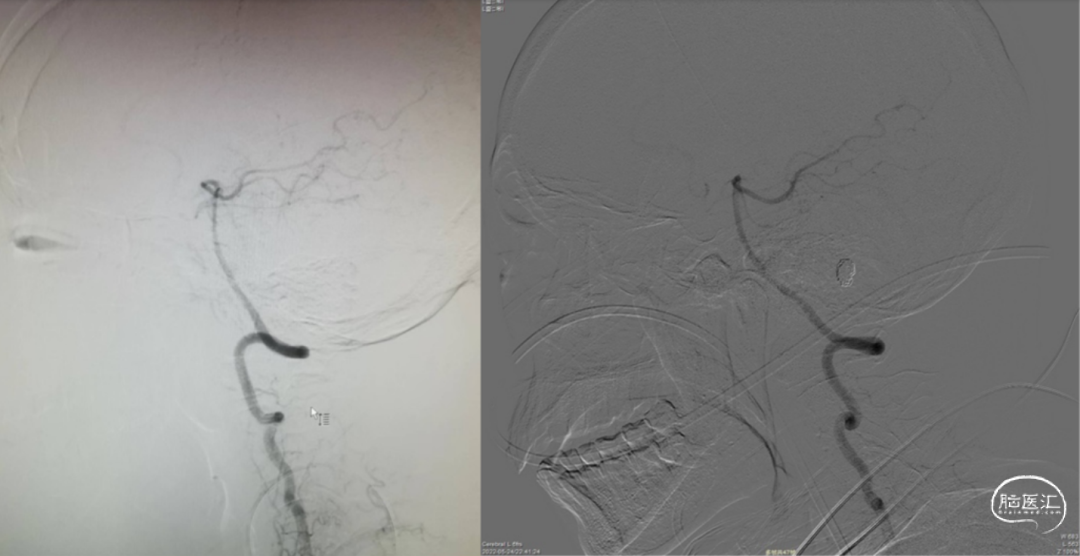

图3.外院(左图)及我院右侧后循环侧位血管造影(右图)提示患者健侧PICA未发育。